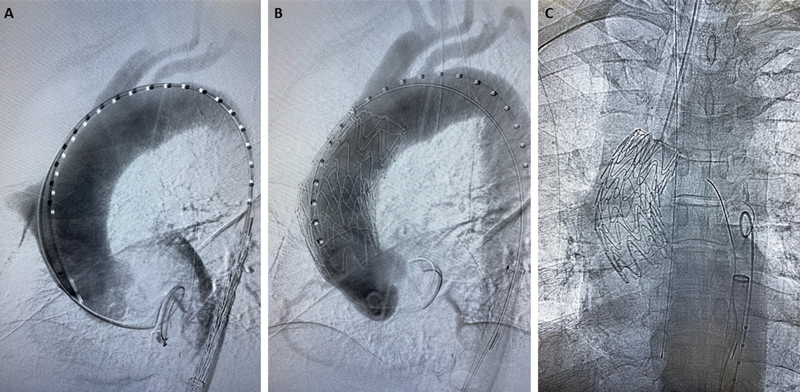

虽然开放手术是升主动脉病变的标准治疗方法,但血管内方法也是可行的选择。我们报告了一例患有 5.7 厘米升主动脉穿透性溃疡的 77 岁男性病例。考虑到患者的年龄和临床特征,他接受了 0 区胸腔内主动脉血管修补术。

Although open surgery is standard of care for ascending aortic pathology, endovascular approaches can be viable options. We report the case of a 77-year-old man with a 5.7-cm ascending aorta penetrating ulcer. Given his age and clinical profile, the patient underwent Zone 0 thoracic endovascular aortic repair.